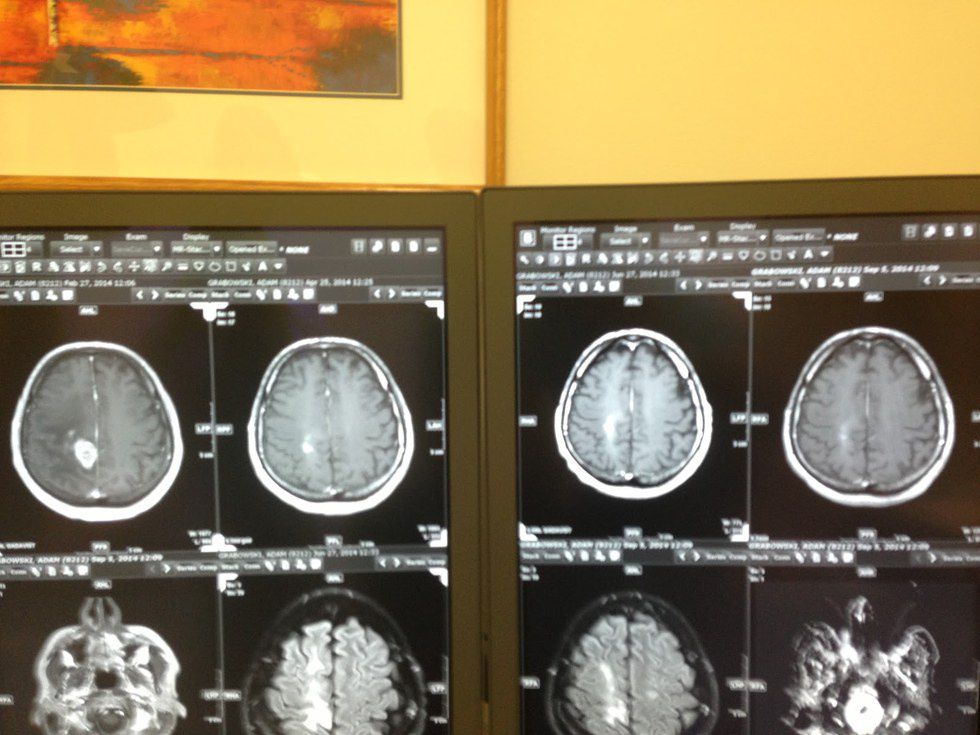

A 43-year-old male glioblastoma patient (which is a type of brain cancer) was asked what he thought of the cancer treatment in the United States to which he responded, “I would have never thought that the States would make it so difficult to treat a disease that is this serious. It is crazy to think about the number of people that are affected by this awful condition as well. The least the States could do is allow for more options, not just chemo and radiation.” He also later stated that the chemotherapy actually did more damage than good, stating that he felt far more weak and depressed rather than energized. His MRIs also showed little improvement as he was doing the suggested chemotherapy and radiation.

The MRI results above are from that same cancer patient that has been mentioned throughout. After his treatment in Germany, there was a significant change in the tumor. On the top left corner, one can see a significant white mass which makes up the tumor; but right next to that there is an MRI result that shows significant improvement after the vitamin infusion treatments done by Dr. Puttich. Although B17 has made a huge impact on many people all over the world, this type of alternative medicine is not the only type of its kind.